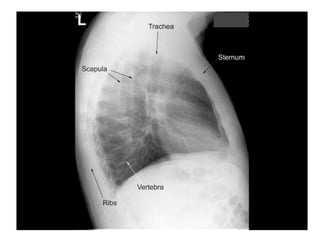

Lateral Film

Left Lateral

Right Lateral